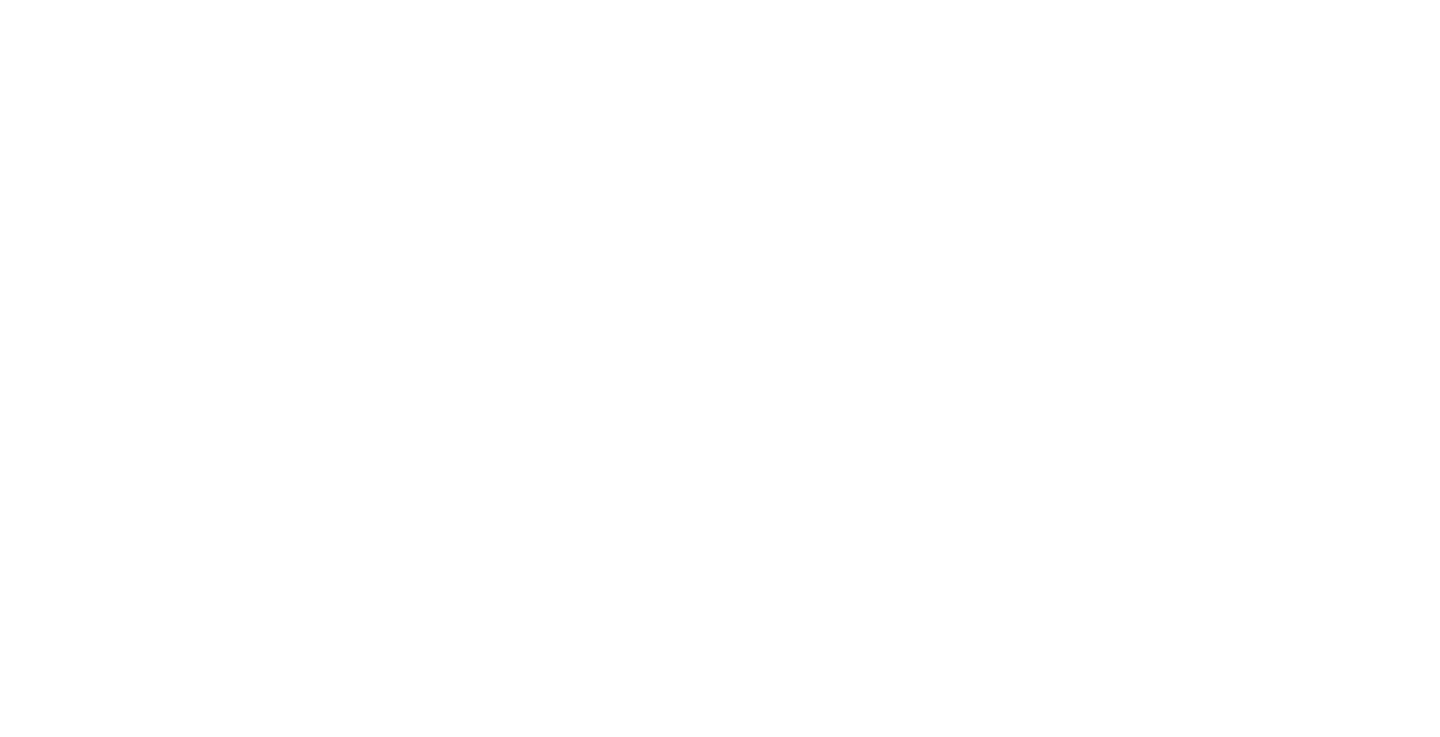

Variant Of Takotsubo Cardiomyopathy Associated With Sepsis And